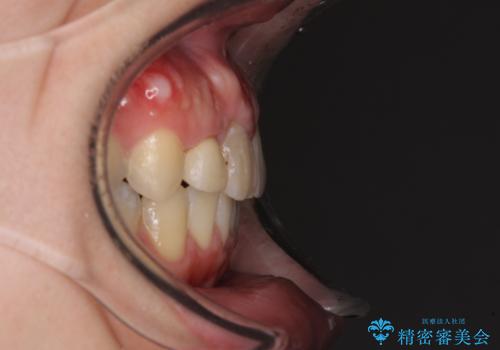

- 上下のデコボコと奥歯の咬みにくさを気にして来院された患者様です。

上顎骨の幅が下顎骨よりも小さいので、拡大装置により骨幅を広げて上下関係を改善し、その後インビザラインにて歯並びを整えることとしました。

上下の骨幅を改善したことで、スムーズに歯列矯正を行うことができました。

奥歯の咬み合わせを改善する必要があったため、治療は長期化しましたが、きっちりと仕上げることができました。